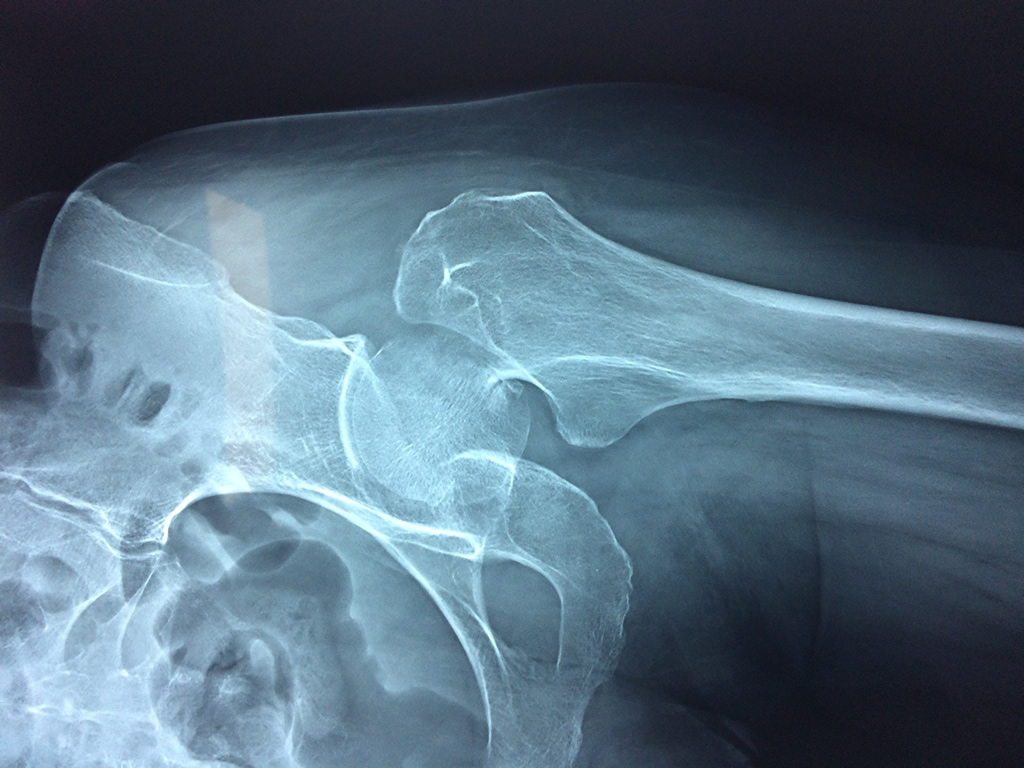

Cirugías de Hombros - Cadera